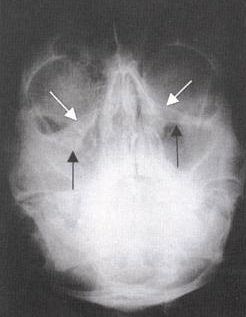

Waters View

Normal

Water Views

Blow-Out Fracture